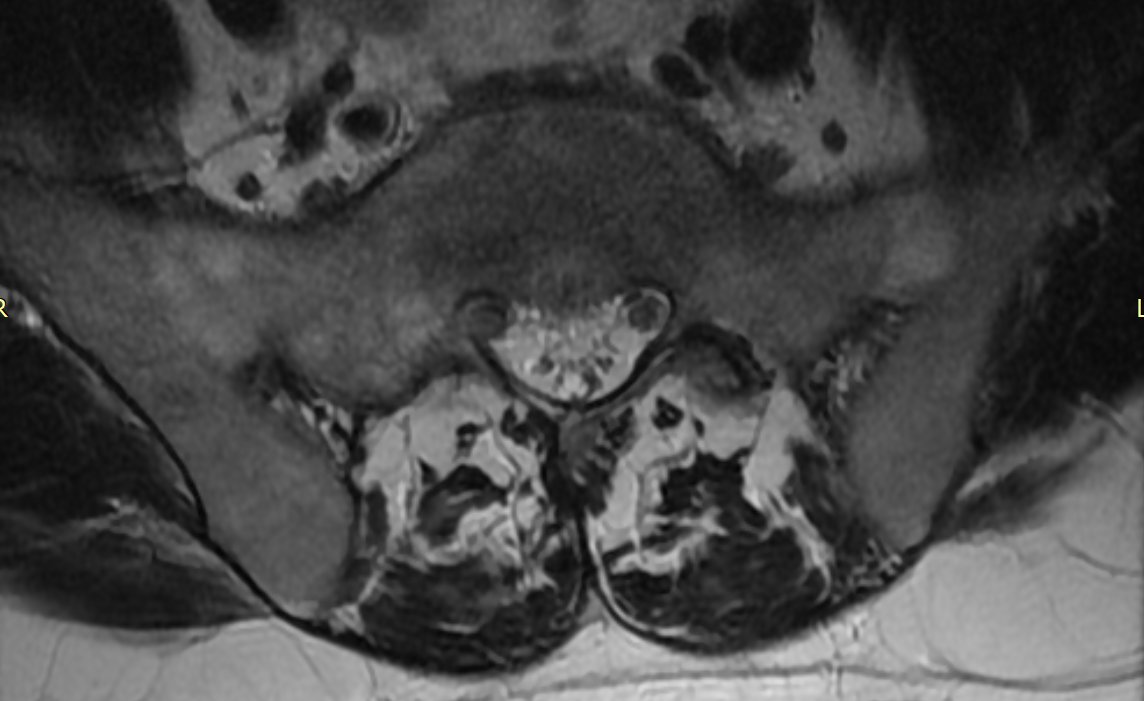

70y/o👩🏾‍🦳.Expansile lession w/mild mass effect on the conus medullaris&cauda equina. Scalloping of the posterior elements. HighT2 signal No DWI anomaly. Most likely spinal(apparently)extradural arachnoid cyst. Same date brain MR:no brain sag nor congestion #spinerad @The_ASSR

josealejandrobv's tweet image. 70y/o👩🏾‍🦳.Expansile lession w/mild mass effect on the conus medullaris&cauda equina. Scalloping of the posterior elements. HighT2 signal No DWI anomaly. Most likely spinal(apparently)extradural arachnoid cyst. Same date brain MR:no brain sag nor congestion #spinerad @The_ASSR